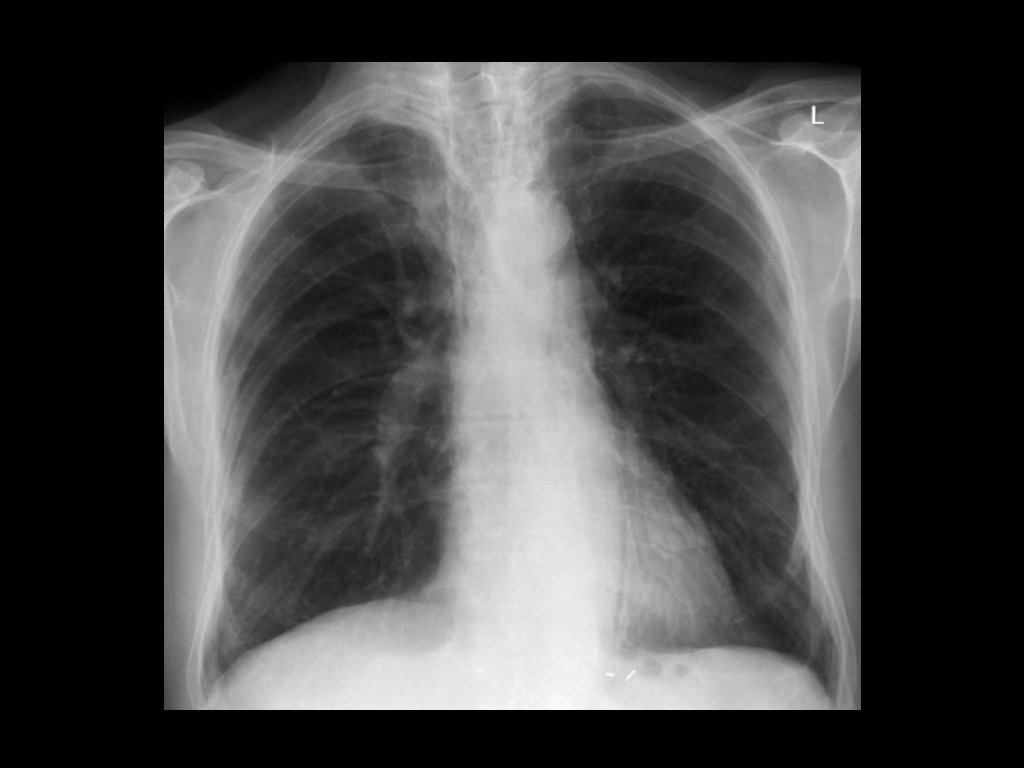

Imaging: • CXR is commonly performed in the evaluation of ED patients with chest pain. • Most patients with ACS have a normal CXR. • Useful to exclude other conditions such as pneumonia and pneumothorax.

Diagnosis: • ECG and CXR: Often non-specific. • Low to moderate risk of having PE → D-dimer. • High risk of having PE → send directly to imaging. • CT pulmonary angiogram is the test of choice.